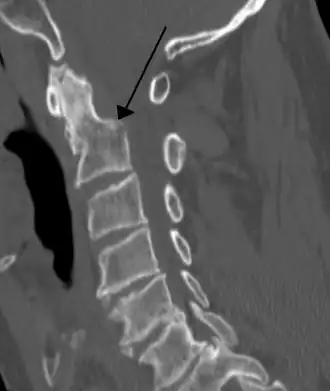

Imagerie

- Rachis cervical de profil : est le cliché de loin le plus utile ; il doit permettre la visualisation de l’occiput au disque C7 –D1[3]. Dans le cas contraire, il faut le refaire. Chez certains patients au cou court, la visualisation de C7 – D1 est impossible. On réalise un cliché dans la position du nageur, mais on court le risque de déplacer une lésion instable[3], et surtout en cas de contexte clinique évocateur (douleur, troubles neurologiques) on passe directement au scanner de la charnière cervico-dorsale[3] ;

Les clichés de rachis cervical sont difficiles à interpréter. Un cliché interprété comme normal peut se révéler pathologique après relecture lorsqu’on recherche une anomalie précise. Un cliché normal et relu comme tel n’élimine pas la présence d’une lésion osseuse ou des parties molles découverte sur des clichés ultérieurs[3]. Cependant, les lésions instables du rachis cervical présentant des risques neurologiques sont visibles sur les clichés initiaux après lecture sérieuse avec un minimum de soin. Le cliché initial de rachis cervical de profil doit permettre d’éliminer un risque de survenue de lésion neurologique s’il est lu correctement. En cas de doute diagnostic, le scanner dont le niveau est orienté par les radiographies est l’examen de choix[3].

Il faut insister sur la détection d’un antélisthésis (déplacement d’un corps vertébral en avant sur le corps vertébral sous jacent) bien visible sur l’alignement des bords postérieurs des corps vertébraux. Un antélisthésis de plus de 2 mm en dessous de C4 et 4 mm au-dessus de C4 est pathologique chez l’adulte. La plupart des lésions osseuses s’accompagnent en règle d’un antélisthésis. Les associations de fractures à des niveaux différents sont fréquentes[3] et il faut les rechercher systématiquement.